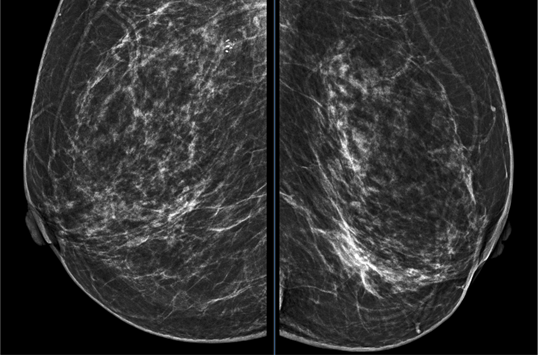

X-quang tuyến vú 2 bên. Hình ảnh đám tăng đậm độ bất xứng ¼ dưới trong bên trái

Tại Bệnh viện Bạch Mai, bệnh nhân được chụp X-quang tuyến vú hai bên, phát hiện vùng tăng đậm độ bất xứng ở 1/4 dưới trong vú trái, xếp loại BIRADS 4. Siêu âm tuyến vú ghi nhận tại vị trí 9 giờ vú trái, cách núm vú 1cm có nhân giảm âm, kích thước 6x3mm (BIRADS 3). Kết quả chọc hút tế bào cho thấy hình ảnh ung thư biểu mô vú, do đó bệnh nhân được chuyển đến Trung tâm Y học hạt nhân và Ung bướu để tiếp tục đánh giá và điều trị.

Các xét nghiệm máu, sinh hóa, chỉ điểm khối u đều trong giới hạn bình thường. Tuy nhiên, kết quả cộng hưởng từ (MRI) tuyến vú hai bên đã cung cấp những thông tin quan trọng. MRI cho thấy vú trái có tổn thương lan rộng 1/2 dưới tuyến vú, thâm nhiễm núm vú (BIRADS 4C). Đáng chú ý, vú phải cũng phát hiện hai tổn thương nhỏ, kích thước từ 5–11mm, được xếp loại BIRADS 4A và 4B.